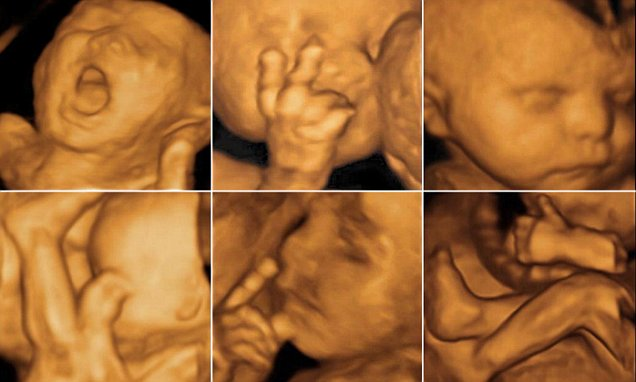

Dacă știi ce este ecografia 3D, atunci cunoști aproape totul și despre ecografia 4D?Pentru că, la fel ca cea dintâi, aceasta oferă posibilitatea de a vedea fătul în spațiu (adică lungime, lățime și înălțime), dar în plus față de prima, ecografia 4D permite vizualizarea produsului de concepție în timp real,timpul fiind cea de-a 4-a dimensiune, de aici unicitatea ecografiei 4D. Adică, efectiv, viitorilor părinți le este permis să vadă mișcările fetale în interiorul uterului. În urma acestui tip de examinare pacienții pot primi un CD cu neprețuitul filmuleț. În sarcină ecografia 4D poate fi utilizată electiv sau având indicații medicale precum evidențierea defectelor de tub neural sau a despicăturilor palatului. Undele sonore sunt trimise în cadrul ecografiei 4D în corp, din mai multe unghiuri (spre deosebire de ecografia clasică 2D, unde se trimit dintr-un singur unghi, generând o imagine plană) și formează o imagine tridimensionala a fătului. Acesta este surprins în timpul vieții intrauterine, astfel că medicul poate aprecia mișcările fetale (ale buzelor si pleoapelor, mișcările respiratorii și deglutiția, de exemplu) și alte detalii: conformația țesuturilor moi, degetele, urechile și, mai cu seamă sexul copilului. Pentru ca îl poate observa aproape ca atunci când l-ar avea în realitate în fața ochilor, medicul poate identifica mai devreme structura anatomica a organelor și eventualele anomalii structurale(de exemplu, spina bifida, despicătura buzelor sau a palatului). O alta caracteristică a ecografiei 4D cât și a ecografiei 3D în sarcină este generarea imaginilor cu o rezoluție de până la 40-60% mai bună decât a celor 2D. Acest lucru ajută medicul în depistarea detaliilor problematice pe parcursul sarcinii.

Când se face ecografia 4D in sarcina?Perioada optimă pentru efectuarea ecografiei 4D este între 24 și 36 de săptămâni. Pentru că acum fătul este suficient de dezvoltat încât să fie vizibil în detaliu și să ii poată fi distinse trăsăturile.